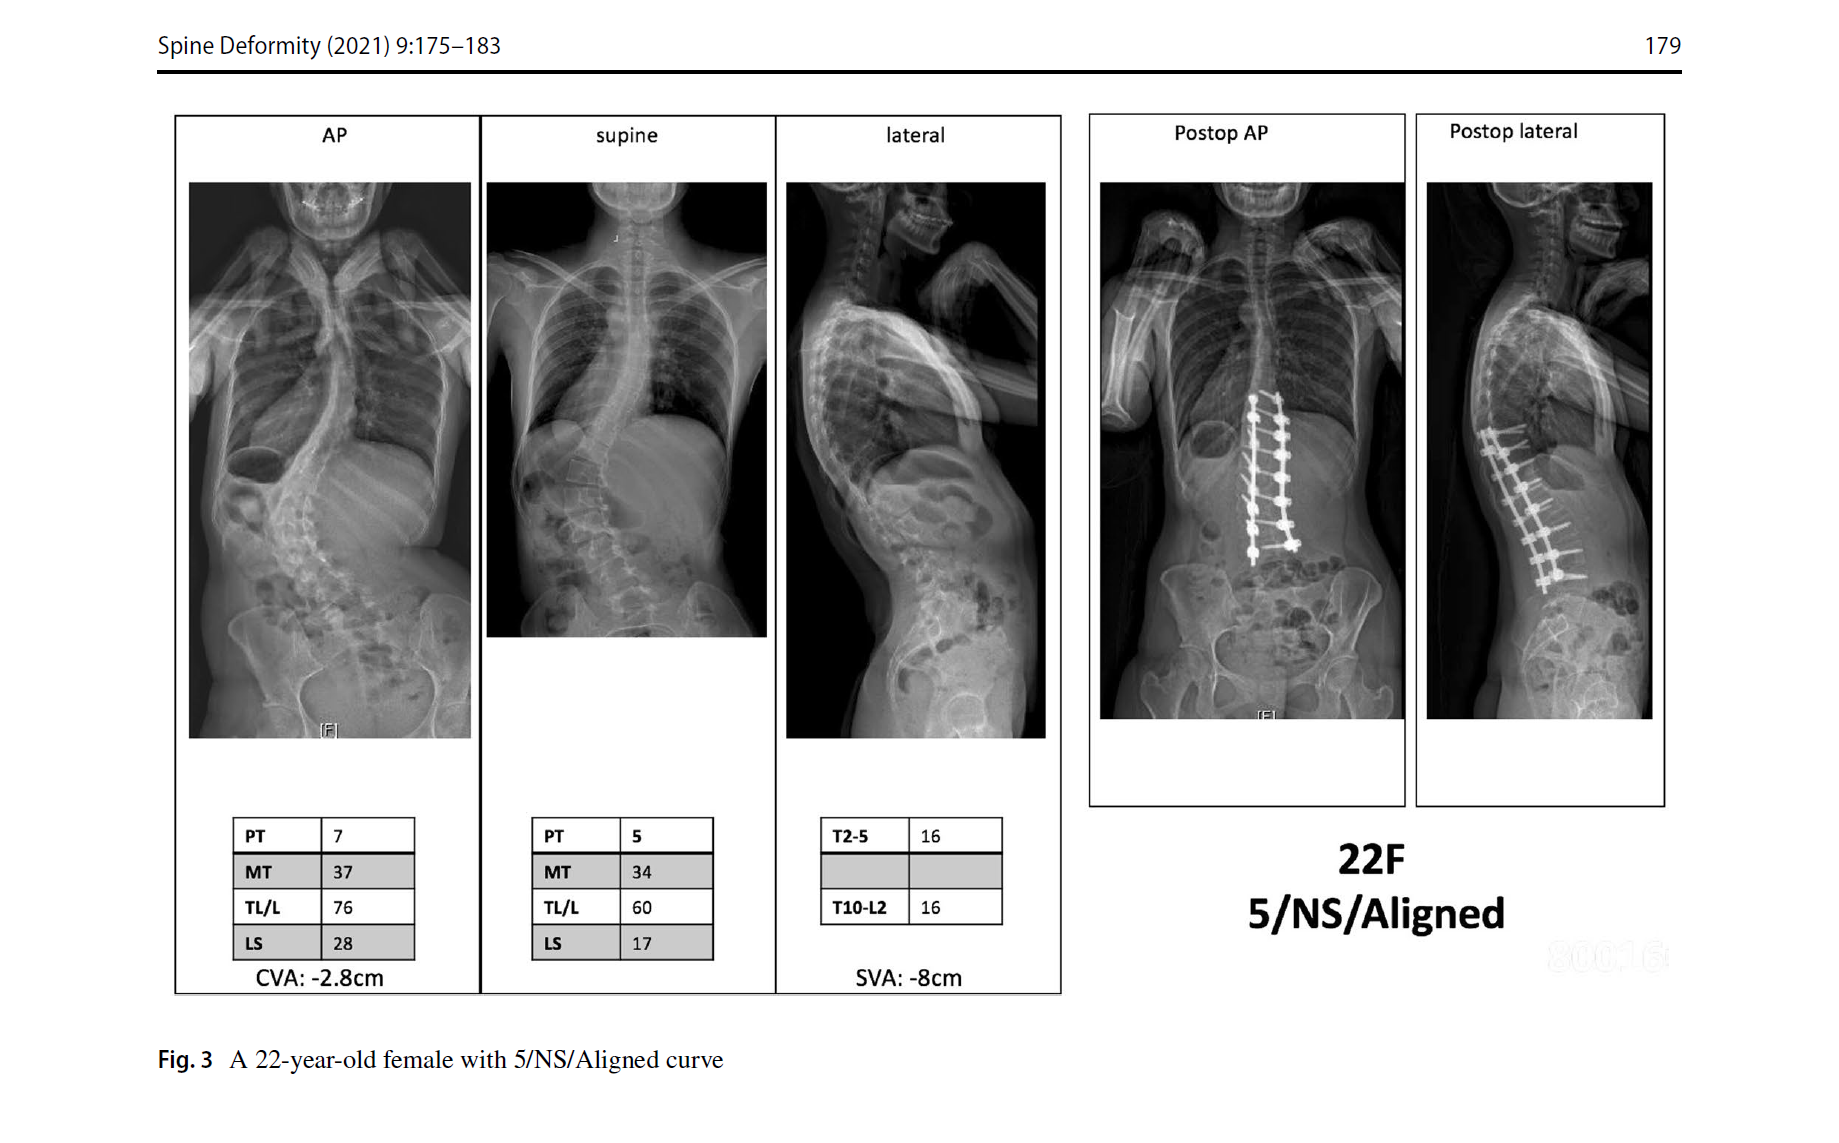

3. 脊柱平衡修正包括了冠状位、矢状位和冠矢合并的平衡状态。标准与SRS基本一致,冠状位失衡CVA≥40mm,矢状位失衡SVA≥40mm。排列组合,共有Aligned、Sag Malalign、Cor Malalign、or Comb Malalign 4种类型。如果脊柱失衡,需要按SRS标准矫正。

文中的病例片子很漂亮,看图知意,很容易让读者理解这个分型。